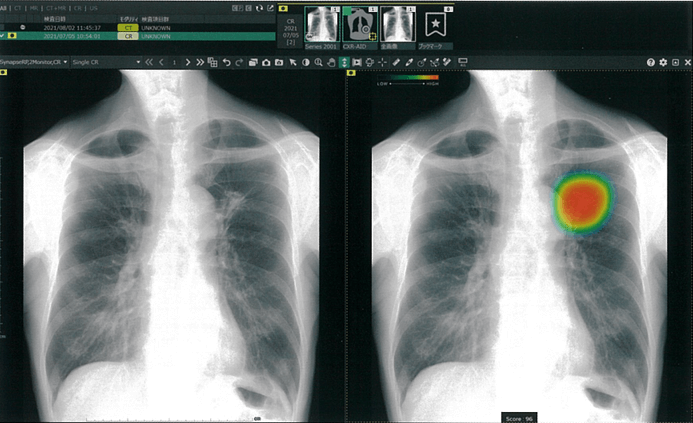

胸部レントゲン検査にAIでサポートする画像病変検出ソフトウェア【富士フィルム社 CXR-AID】を導入しました

胸部レントゲン検査は、健診や通常診療時に肺癌や肺炎、心臓疾患などの検査として実施されます。これらの病気は早期発見と早期治療介入が非常に重要です。この度、『そのような病気をより早期に発見したい』『より小さく、分かりにくい病変の見落としを防ぎたい』という思いから、AIで画像診断をサポートする画像病変検出ソフトウェアを導入しました。

【CXR-AID】は撮影した胸部レントゲン画像をAI技術を活用して自動解析し、結節・腫瘤影、浸潤影、気胸が疑われる領域を検出し、マーキングします。【CXR-AID】の導入により、胸部疾患のより精度の高い診断を行い、早期発見・早期治療が促進され、患者さんの健康管理に大きく貢献することが期待されます。